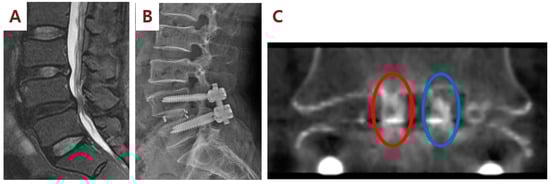

2.3. Spinal Fusion Surgery and SVF Implantation

3.2. Clinical and Radiographic Outcomes